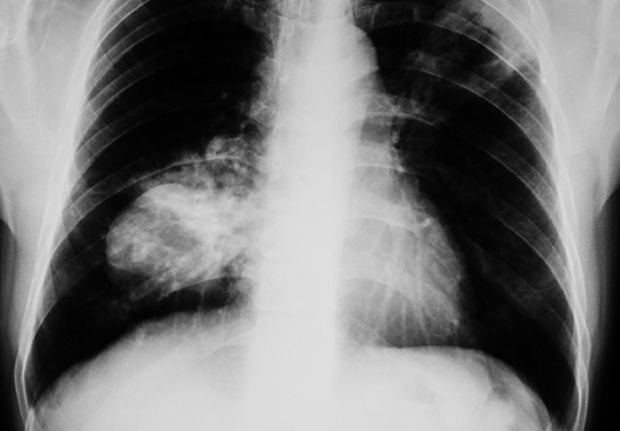

Džin je radila testove krvi, skeniranja i rendgenske snimke prije nego što su doktori shvatili da se bori sa rakom pluća. Nakon uspostavljanja dijagnoze, Džin je otkrila znak upozorenja koji nikada ne smete zanemarivati. Krivljenje i savijanje noktiju, može biti indikator kancera.